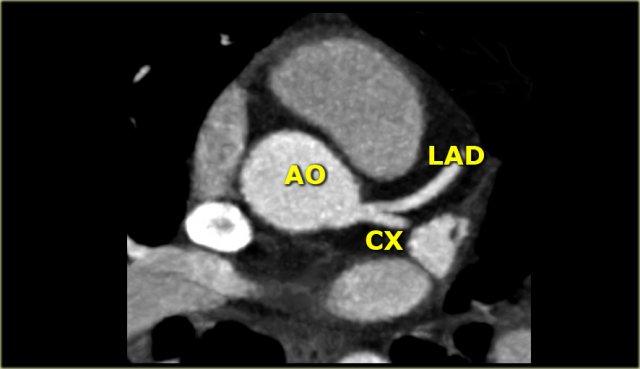

Bên trái là hình ảnh CT cắt ngang.

LCA đi giữa đường ra thất phải ở phía trước và nhĩ trái ở phía sau, rồi phân chia thành LAD và Cx.